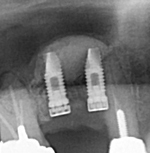

レントゲン写真

治療前 レントゲン写真

治療後 レントゲン写真